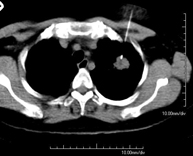

Prueba diagnóstica que consiste en obtener imágenes del tórax de alta definición anatómica (pulmones, corazón, mediastino, grandes vasos, caja torácica, etc.) mediante el empleo de un equipo de TC (Tomografía Computarizada). Dichas imágenes se estudian posteriormente en una estación de trabajo que permite reconstrucciones bidimendionales en diferentes planos del espacio y también reconstrucciones 3D (volumétricas). Algunos estudios requieren el empleo de contraste yodado para mejorar la definición de las imágenes. - Angio-TC Aorta torácica

Prueba diagnóstica que consiste en el estudio de la aorta torácica (principal arteria del tórax) mediante el empleo de un equipo de TC (Tomografía Computarizada). Esta técnica requiere el empleo de contraste yodado, y proporciona imágenes de alta definición anatómica. El uso del TCMD (TC Multidetector) acorta el tiempo de exploración, disminuye la dosis de radiación y mejora la calidad de la imagen. Gracias a los múltiples detectores, en determinados estudios se puede acoplar la obtención de la imagen con el latido cardíaco, técnica que permite el estudio de la válvula aórtica y de la raíz de la arteria aorta (primeros centímetros), donde el latido del corazón suele provocar múltiples artefactos de movimiento. - Angio-TC Arterias pulmonares (Estudio TEP, Tromboembolismo Pulmonar)